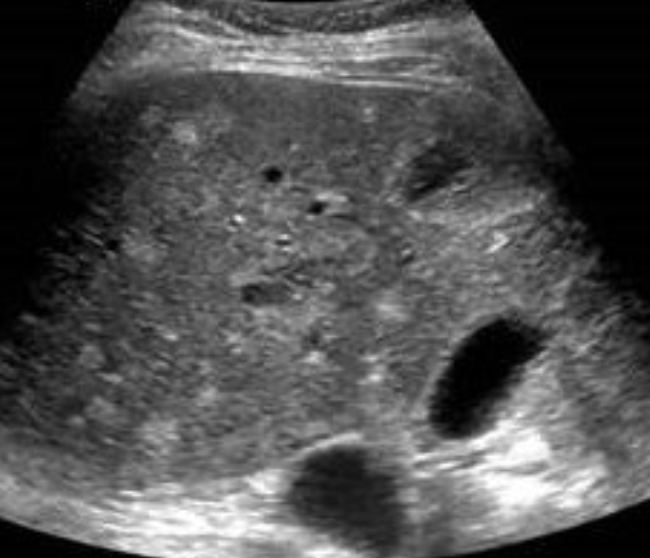

HCC (Hepatocellular Carcinoma) → most common primary malignant neoplasm of the liver

clinical hx: cirrhosis, HBV, HCV, men

s/sx: asymptomatic until invasion, weight loss, abdominal swelling (secondary to ascites), elevated serum AFP

2D US: hypoechoic, echogenic, complex/heterogenous, usually solitary massive tumor, can be multiple nodules throughout the liver, diffuse infiltrative mass, ascites; **fibrolamellar carcinoma has same appearance, but in adolescents

color doppler: very vascular, vascular lumen invasion in both hepatic and portal veins